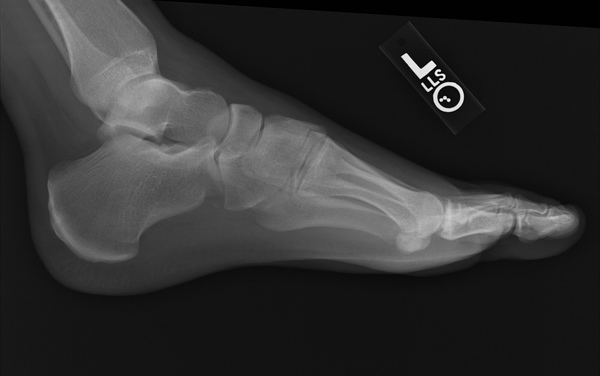

Bir ayağınızda ya da her iki ayağınızda da kronik ağrı hissediyorsanız bunun nedeni topuk dikeni olabilir. Kulağa korkutucu gelse de tedavi edilebilir.

Topuk dikeni, ayağınızı aşırı acıtır. Kendiliğinden geçmesi ise bir yılı bulabilir.

Topuk dikenine sahip olan kişiler acıyı birilerinin ayaklarına neşter batırması gibi tarif ediyorlar.